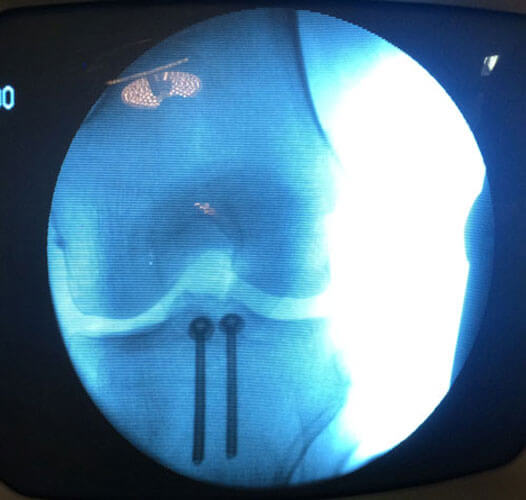

Arthroscopy Surgery